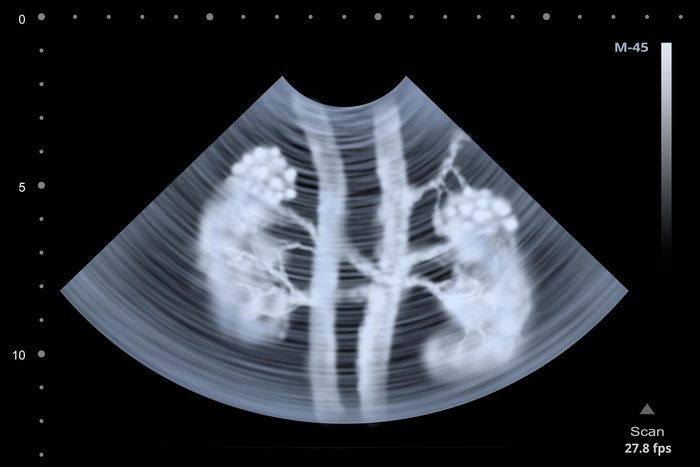

What is kidney cancer?

You have two kidneys—they’re bean-shaped organs located below your rib cage on each side of your spine. Your kidneys contain tubules that filter out waste from your blood and convert it to urine—the primary role of your kidneys. It’s in these tubules that things can go wrong and trigger the signs of kidney cancer: “The most common type is renal cell cancer, which originates in the tubules,” says Jason Abel, MD, urologic surgeon and member of the UW Carbone Cancer Center.

That doesn’t mean the cancer is always caught late. “People can get imaging scans like MRIs or ultrasounds for completely unrelated reasons [that reveal a tumor], so at least two-thirds of these patients are diagnosed when the cancer is very small,” says Dr. Abel. That’s a good thing; cancer caught early is more effectively treated. Learn about the 7 silent signs your kidneys are in trouble.